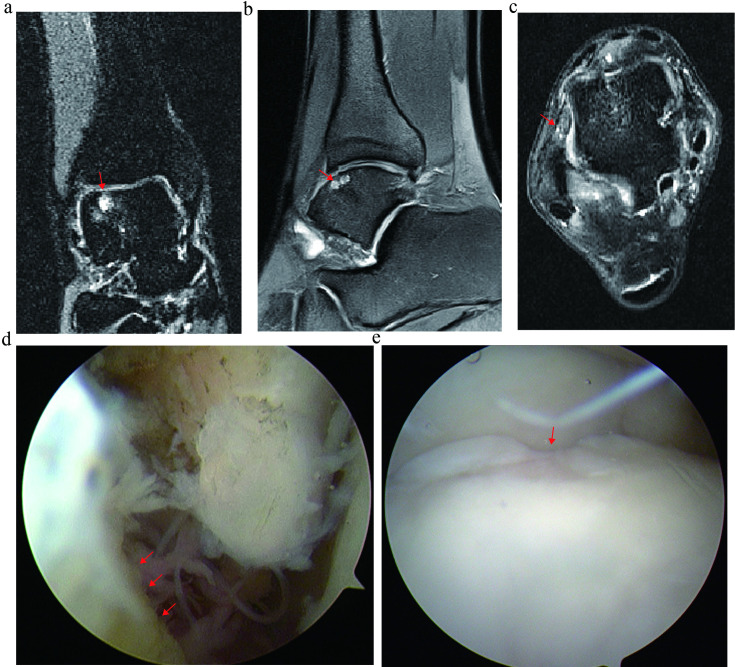

Abstract Image